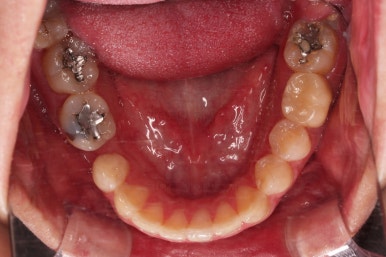

초진 시 입안의 모습입니다.

화살표는 결손 부위, 동그라기믄 유치잔존과 매복치아 부위입니다.

아래 어금니쪽은 선천결손이었고요.

동그라미는 유치가 있는 상황이었는데요. 잇몸도 많이 파괴되어 있었고, 유치 자체의 상태도 좋지 못했어요.

동그라미 부분은 상한 유치가 보이는데, 그 하방으로 영구치가 매복되어 올라오지 못하고 있는 상태였어요.